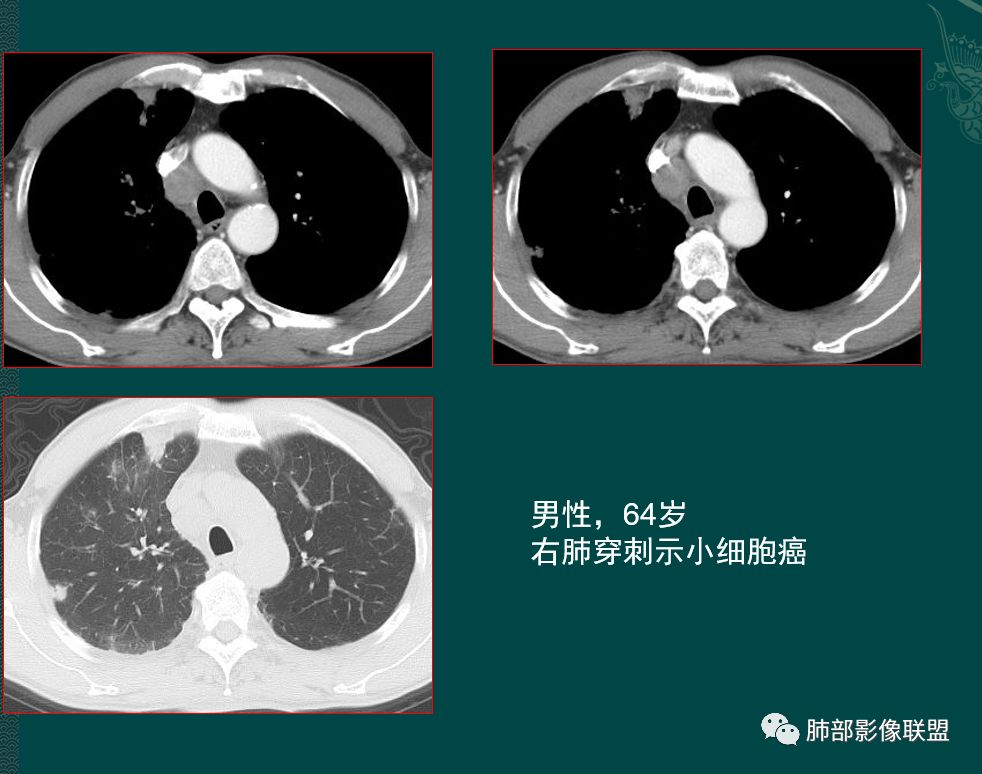

小细胞肺癌SCLC起源于支气管粘膜下,沿支气管粘膜下及周围血管生长,病理上SCLC细胞较小,胞质很少,粘附力差,肿瘤质软,细胞密集,增值快,侵袭生长,坏死小,常不彻底,破坏力弱。

有人认为SCLC以周围型多见,部分周围型SCLC因借肺门显著增大的淋巴结而摇身一变,以“中央型”的姿态出现在我们的视野中。

1鸭蹼状突起、腊肠样尾巴、指状突起、蠕虫、分支及条状

因为病灶沿支气管粘膜下及周围血管生长,走形方向与支气管一致,所以支气管血管周围生长也是SCLC的典型征象;

2娘小崽大、淋巴及血行转移早、冰冻纵隔及肺门血管脂肪间隙消失

因为病灶侵袭力强,病灶易沿淋巴道、间质及心血管间隙等结构侵犯并密切挤压上述结构,常常能够观察到脂肪间隙消失。易于出现冰冻纵隔。原发灶与肺门转移灶可形成哑铃状外观,甚至转移灶体积大于周围原发灶,有人称之为“娘小崽大”。早期病灶有时很小甚或隐匿,仅能看到转移灶,或转移淋巴结与原发灶融合分界不清。病变向肺门延续的串珠样淋巴结转移也是SCLC的典型特点。

病灶侵袭力强大,早期沿粘膜下疏松结缔组织及血管旁间隙扩散,包绕血管,间隙消失,血管会受压变形,因为小细胞癌破坏力弱,血管没有被破坏,所以仅仅表现为包埋浸润,但血流面光滑。

乏血供,沼泽样坏死

病灶肿瘤密集而供血血管相对不多,密度较均匀,轻度强化,呈乏血供,有时候可以坏死,坏死不彻底,坏死区分散而较小,呈沼泽样坏死。很难造成较大范围引流支气管的破坏,所以空洞罕见。

发生于肺边缘的小细胞癌有时会呈半圆形或圆冠状贴服于胸壁下,有老师称之为“山丘征”。经治疗后复查持续存在或增大的山丘影应当想到小细胞肺癌的可能性,尤其是在肺门纵膈淋巴结增大时。

位于胸膜下的周围型Sclc沿着胸膜塑形成长:长轴贴于胸膜面,一侧或双侧与胸膜交为钝角,不侵及相邻肋骨,似山丘状或馒头状(馒头质地软)

我最近统计的周围型小细胞癌,位于胸膜下的,竟然没有1例侵及肋骨,由此可见小细胞癌的柔软性。

长在胸膜下,就像一滩泥一样,塑形生长。